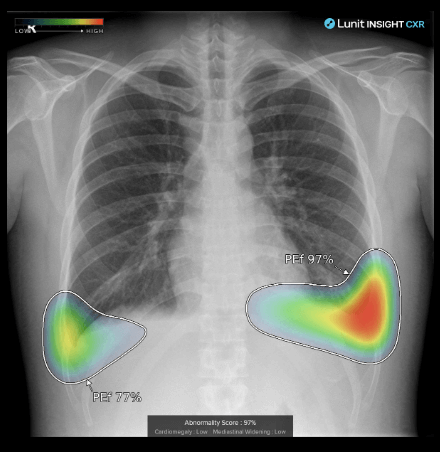

주요 사업은 루닛 인사이트와 루닛 스코프라는 솔루션이 있습니다. 루닛 인사이트는 암진단 솔루션이며, 루닛 스코프는 항암제 치료 효과 예측 솔루션입니다.